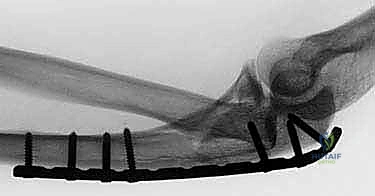

TECH FIG 2 • A,B. Preoperative and postoperative radiographs demonstrating open reduction and internal fixation of the radial head component of the Monteggia fracture.

TECH FIG 2 • ( continued ) C. Postoperative radiograph of a Monteggia fracture in which the radial head fracture needed to be replaced.

TECH FIG 2 • ( continued ) C. Postoperative radiograph of a Monteggia fracture in which the radial head fracture needed to be replaced.

TECH FIG 3 • ( continued ) D. Final fixation for most Monteggia fractures is with a rigid plate applied to the dorsal cortex.

TECH FIG 3 • ( continued ) D. Final fixation for most Monteggia fractures is with a rigid plate applied to the dorsal cortex.